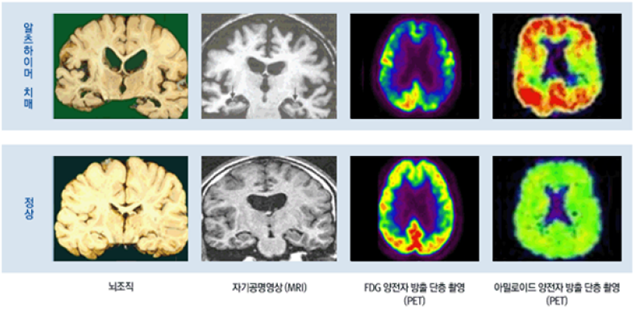

Weinstein이 2급 살인(모살, 계획적이진 않지만 의도된 살인)으로 기소되자 그의 변호인은 그의 뇌영상 자료를 법원에 제출하면서 정신질환으로 인한 책임무능력을 이유로 무죄를 주장하게 됩니다.

<정상인의 뇌(좌측)와 Weinstein의 뇌(우측) 비교 촬영 사진>

위 영상 자료 왼쪽이 일반 정상인의 뇌를 촬영한 것이고 오른쪽이 당시 제출된 Weinstein의 뇌 영상 자료인데, 뇌 자기공명 영상(MRI) 및 양전자 단층촬영(PET) 결과 그의 좌측 전두엽에 사진처럼 오렌지 크기만한 지주막 낭종이 발견되었고, 낭종이 있는 부위의 포도당 대사 수준이 저하되어 있어 범행 당시 Weinstein이 ‘전두엽 기능장애’ 상태에 있었다는 것입니다. 이와 같은 변호인의 무죄 주장은 특정 순간에 저지른 특정 행위와 뇌손상을 연결 짓는 최초의 시도였습니다.

법원에서 Weinstein의 책임무능력을 인정하지는 않았으나, 위와 같은 뇌 손상 주장이 일부 받아들여져 애초 기소된 2급 살인인 모살보다 형이 낮은 고살(계획과 의도가 없는 우발적 범죄)의 부정기형(단기 7년, 장기 21년)이 선고되었습니다.